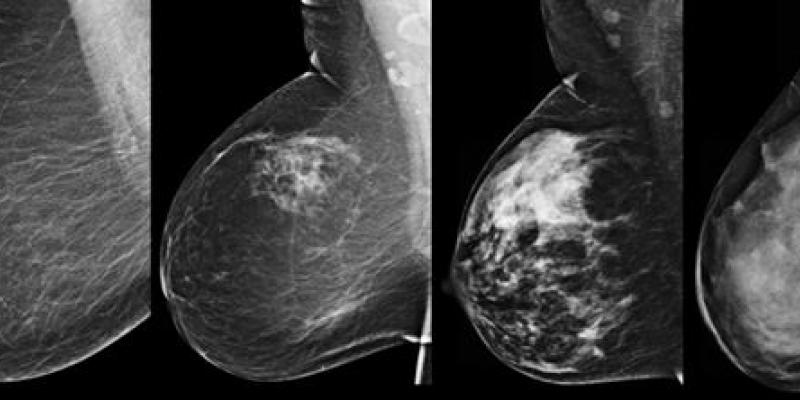

El cáncer de mama representa la primera causa de muerte entre mujeres mexicanas. Pero, esto está a punto de cambiar, ya que gracias al estudio de la ingeniería biogenética, científicos de la Universidad Nacional Autónoma de México (UNAM) han descubierto que lo que genera el desarrollo del cáncer de mama en hombres y mujeres, podría ser un gen en específico. Lo mejor, es que esta revelación permitirá modificar algunos tratamientos en pacientes actuales. Mientras que en un futuro no muy lejano, podría llegarse a editar de la secuencia del genoma.

En términos simples, esta tecnología es capaz de añadir, sustituir, editar o reparar genes ausentes o deficientes para el bienestar de las personas. Tal como en el caso del cáncer de mama, donde expertos de la UNAM y el Instituto Nacional de Medicina Genómica, descubrieron que una alteración del gen ‘AKT1-E17K’, podría ser la causa del desarrollo de esta terrible enfermedad responsable de la muerte de al menos 100 mil personas al año, señalan datos de la Organización Mundial de la Salud.

Sandra Lorena Romero Córdoba, investigadora del Instituto de Investigaciones Biomédicas (IIBm) de la UNAM, y titular de la investigación, recalcó que el 8% de cada 200 pacientes hispanoamericanas, tratadas en la Fundación de Cáncer de Mama (FUCAM), presentó el gen denominado ‘AKT1-E17K’, incluyendo uno de cada 100 hombres.

Posteriormente, esta información fue comparada con bases de datos públicas de pacientes afroamericanas, caucásicas (EU y Europa), así como asiáticas, descubriendo que en estas poblaciones, el gen ‘AKT1-E17K’, solo está presente en el cuatro por ciento del total de las pacientes. Por lo que esta investigación sin precedentes, no solamente confirma que el desarrollo de cáncer –en cualquiera de sus variantes- está estrechamente vinculado a la mutación genética, sino que también revela que podría estar cerca una nueva opción terapéutica para estas pacientes y en un futuro no muy lejano, la erradicación total del cáncer de mama con la edición de esta mutación.